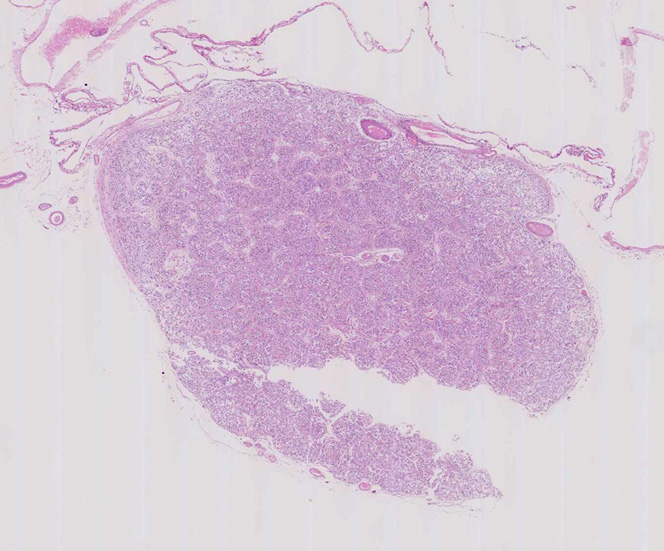

松果体の組織像

normal pineal gland tissue